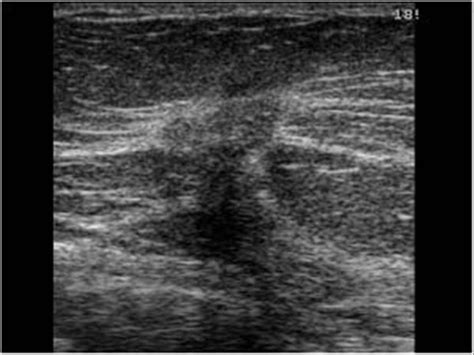

Invasive ductal carcinoma (IDC) is the most common type of breast cancer. It starts in the milk ducts and then invades the surrounding breast tissue. Invasive means the cancer cells have spread beyond the ducts into nearby tissues. Metastatic , on the other hand, means the cancer has spread from the breast to other parts of the body, such as the bones, lungs, liver, or brain. This spread occurs when cancer cells break away from the original tumor and travel through the bloodstream or lymphatic system to other areas.

When we talk about metastatic invasive ductal carcinoma , we’re referring to a cancer that originated in the milk ducts, invaded the surrounding breast tissue, and then spread to distant organs or tissues. This is a more advanced stage of breast cancer, typically stage IV. The location of the primary tumor (in this case, the left breast) is also an important detail for accurate diagnosis and coding.

Early detection through regular screening, such as mammograms, and prompt diagnosis are vital in preventing the progression of invasive ductal carcinoma to the metastatic stage. When breast cancer is detected early, treatment is often more effective, and the chances of a full recovery are higher. So, regular check-ups and awareness of breast health are key.